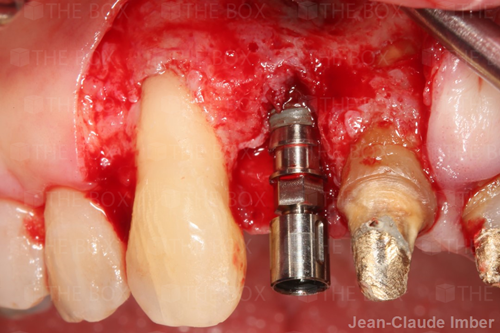

A new case was made public by Jean-Claude Imber check it out here.